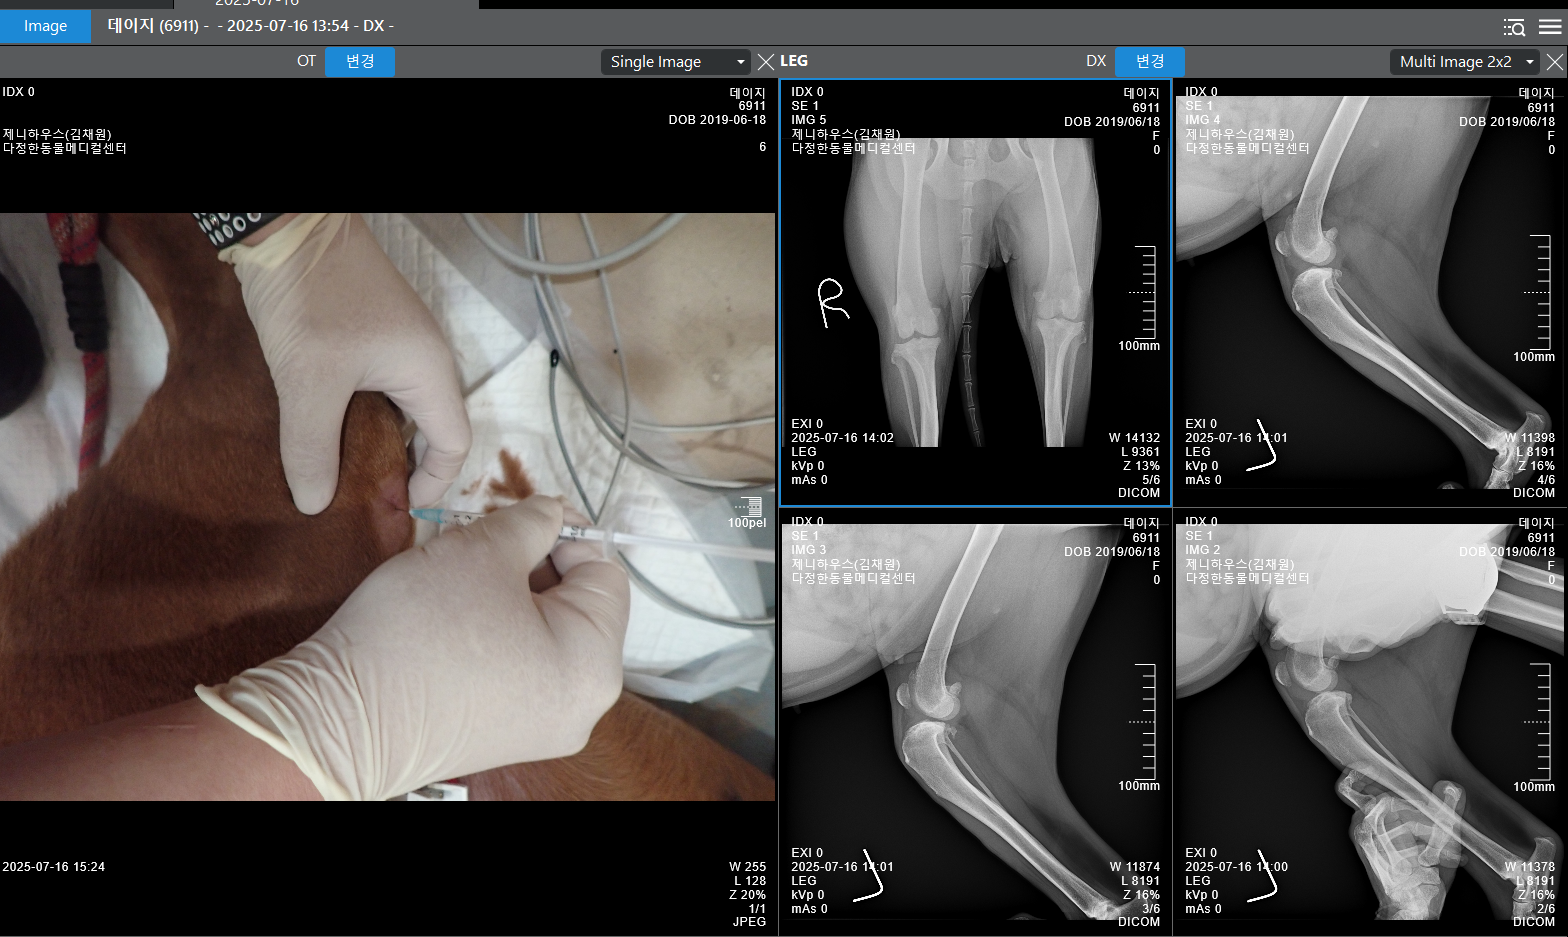

다정한동물메디컬센터에서 검진과 치료를 받기 시작했어요.

관절낭 주사, 약물치료, 그리고 체중 관리까지 진행하고 있었는데요,

마침내, 9월 4일! 다시 한번 연맹의 도움으로 데이지는 TPLO 수술을 받았습니다.